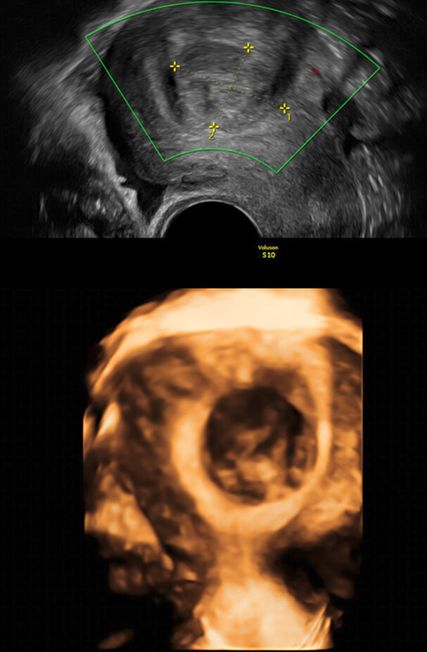

Die Prävalenz angeborener Uterusmalformationen wird mit bis zu 6,7% in der Allgemeinbevölkerung angegeben; bei infertilen Frauen oder solchen mit wiederholten Aborten beträgt sie über 7% bzw. etwa 17%.1 Da die klinische Beurteilbarkeit starken Einschränkungen unterworfen ist, ist die Bildgebung in der Diagnostik zentral. Während die 2D-Sonografie ubiquitär verfügbar ist und zur Abklärung von nichtuterinen Strukturen meist ausreicht, zeigt die 3D-Sonografie eine höhere Sensitivität und Spezifität von 98,3% bzw. 99,4%.2 Während im zweidimensionalen Querschnitt z.B. ein Uterus (sub-)septus von geübten Untersucher:innen am typischen Katzen- oder Eulenaugenphänomen erkannt werden kann (Abb. 1), ermöglicht es die 3D-Sonografie, eine virtuelle koronare Ebene der Gebärmutter zu visualisieren. Sie eignet sich somit optimal zur Diagnostik, aber auch zur Therapieplanung und postoperativen Kontrolle im Rahmen hysteroskopischer Eingriffe wie einer Septuminzision.

Abb. 1: Eulenaugenphänomen bei Uterus (sub-)septus, zweidimensionale Darstellung, Transversalebene